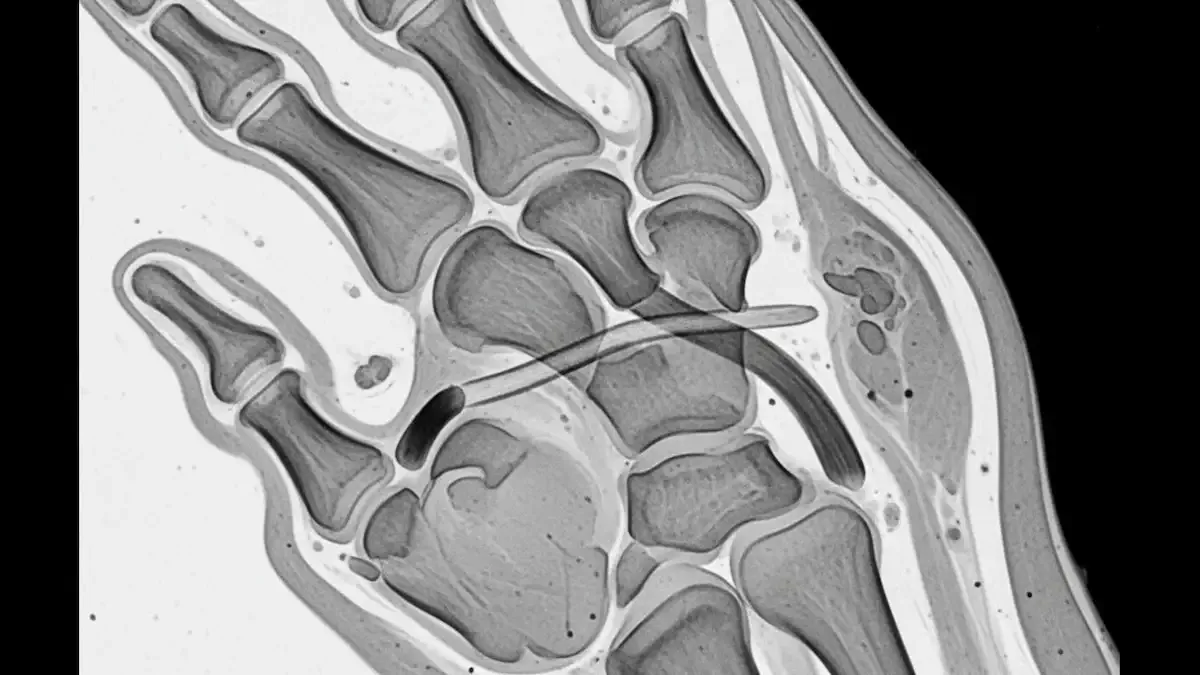

Radiografia, ultrassom e ressonância: quando entram

A radiografia não “mostra” o ligamento, mas é útil para procurar fraturas associadas, principalmente fratura por avulsão na base da falange.

Já o ultrassom e a ressonância magnética conseguem avaliar o ligamento e podem identificar se existe deslocamento compatível com lesão de Stener.

A ressonância costuma dar uma visão mais completa, com maior custo e, às vezes, mais demora para agendar.